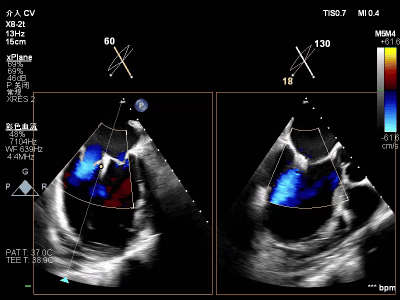

【术中操作(含关键步骤超声)】

鉴于患者术前心功能差、多支架植入的特殊情况,手术全程需兼顾“精准操作”与“保护心功能”双重要求:在全麻与经食道超声的协同引导下,团队先突破心功能受损导致的术野稳定性难题,稳步经心尖建立手术轨道与输送鞘;随后聚焦二尖瓣2偏3区精准置入一枚Ⅱf型夹合器,成功攻占这一解剖位置深、毗邻结构敏感、容错率极低而操作难度陡增的区域。

术前术后反流对比